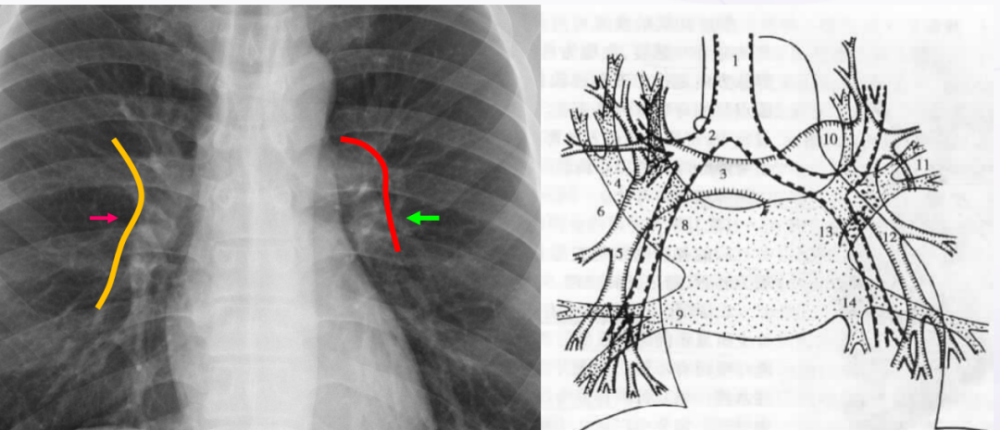

胸片肺门

影像解剖入门正常胸片怎么看